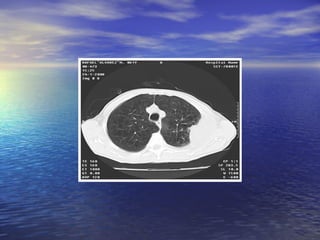

Radiografía y Espirometría

• Imagenes lineales en campos inferiores y

engrosamiento de pleural

parietal→calcifican (>20 años)

Radiografía y Espirometría •Imagenes lineales en campos inferiores y engrosamiento de pleural parietal→calcifican (>20 años) • Altera precozmente la espirometría: patron restrictivo.